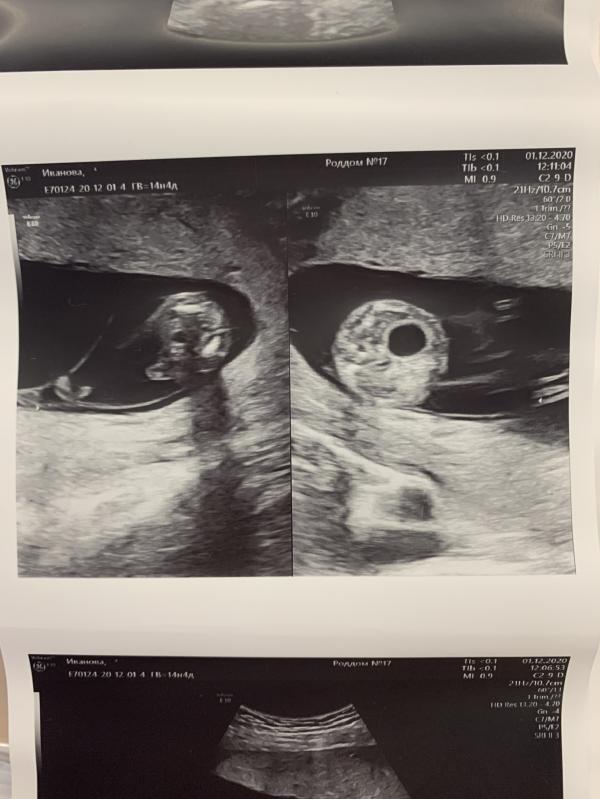

Итак, срок 14.4.

Пройдено очередное плановое УЗИ в 17 роддоме. На этот раз у Каштановой.

Дискордантность сохраняется 30%. Вес малышей 85 г и 122 г. Мочевой у второго большой, по фото видно разницу. Наблюдаемся дальше. Следующее УЗИ в МГЦ на Тобольской 10-11 декабря. Потом опять в 17 роддом 15 декабря. Очень часто видимся с малышами, но УЗИ я не боюсь, да и динамику надо наблюдать ☝🏻